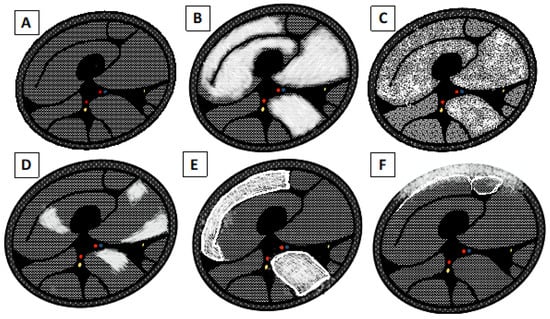

3.1.2. Chronic Changes

- 0 = Normal intensity appearance of the muscle.

- 1 = Early moth-eaten appearance with scattered small areas of high intensity on T1-weighted imaging.

- 2a = Late moth-eaten appearance, with numerous areas of high intensity on T1-weighted imaging, with beginning confluence comprising less than 30%.

- 2b = Late moth-eaten appearance, with numerous areas of high intensity on T1-weighted imaging, with beginning confluence comprising 30–60%.

- 3 = Washed-out, fuzzy appearance due to confluent areas of increased intensity in T1-weighted imaging, with muscle still present at the periphery.

- 4 = End-stage appearance; all muscle replaced by fat with high intensity in T1-weighted.